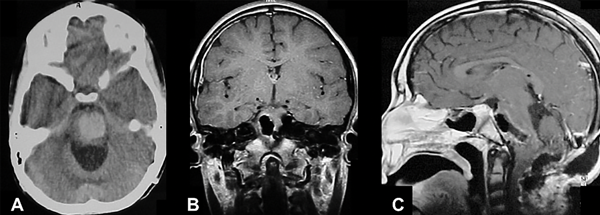

Figura 4. Cavernoma del tronco del encéfalo. Paciente masculino de 11 años, antecedentes de cirugía de resección parcial del cavernoma en dos oportunidades e hidrocefalia que requirió sistema de derivación ventriculoperitoneal. Ingresó por déficit neurológico focal progresivo que agregó trastornos deglutorios, episodios de apneas y paro cardiorrespiratorio, por lo que se realizó la revisión valvular, sin mejoría, para luego efectuar cirugía de resección del cavernoma. Resección completa. Paciente evoluciona favorablemente recuperando función respiratoria y parcial del déficit motor. A) TC de cerebro de urgencia sin contraste que muestra sangrado bulboprotuberancial extenso. B) RM postoperatoria de cerebro con contraste EV, corte coronal, lecho quirúrgico libre de lesión. C) Corte sagital del mismo estudio, nótese el trayecto de disección, generando imagen de tronco “atravesado”.